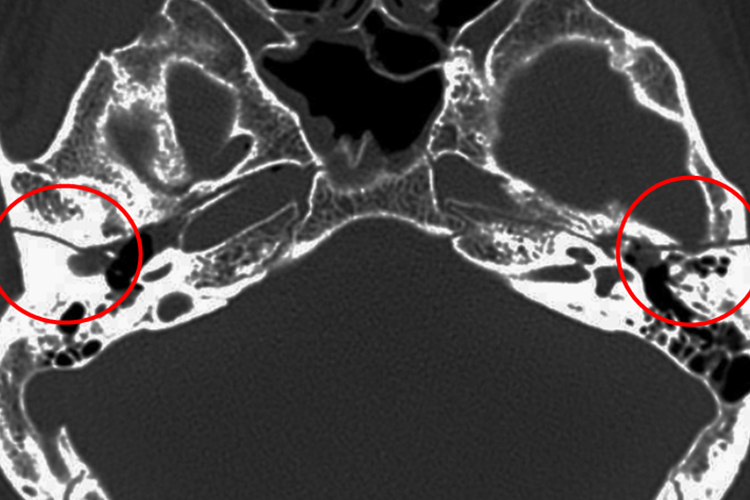

颞骨骨折CT表现为颞骨处有明显的骨折线,多见于骨折线与岩锥长轴平行,并可合并听小骨的脱位、骨折和面神经管的损伤,称为纵行骨折。少数的骨折线与岩锥长轴垂直,呈前后走行,称为横行骨折。另外,也可见于纵、横骨折皆有,常伴有脑损伤,并出现鼓室、乳突气房积液、听小骨脱位、颅内积气、血肿等。